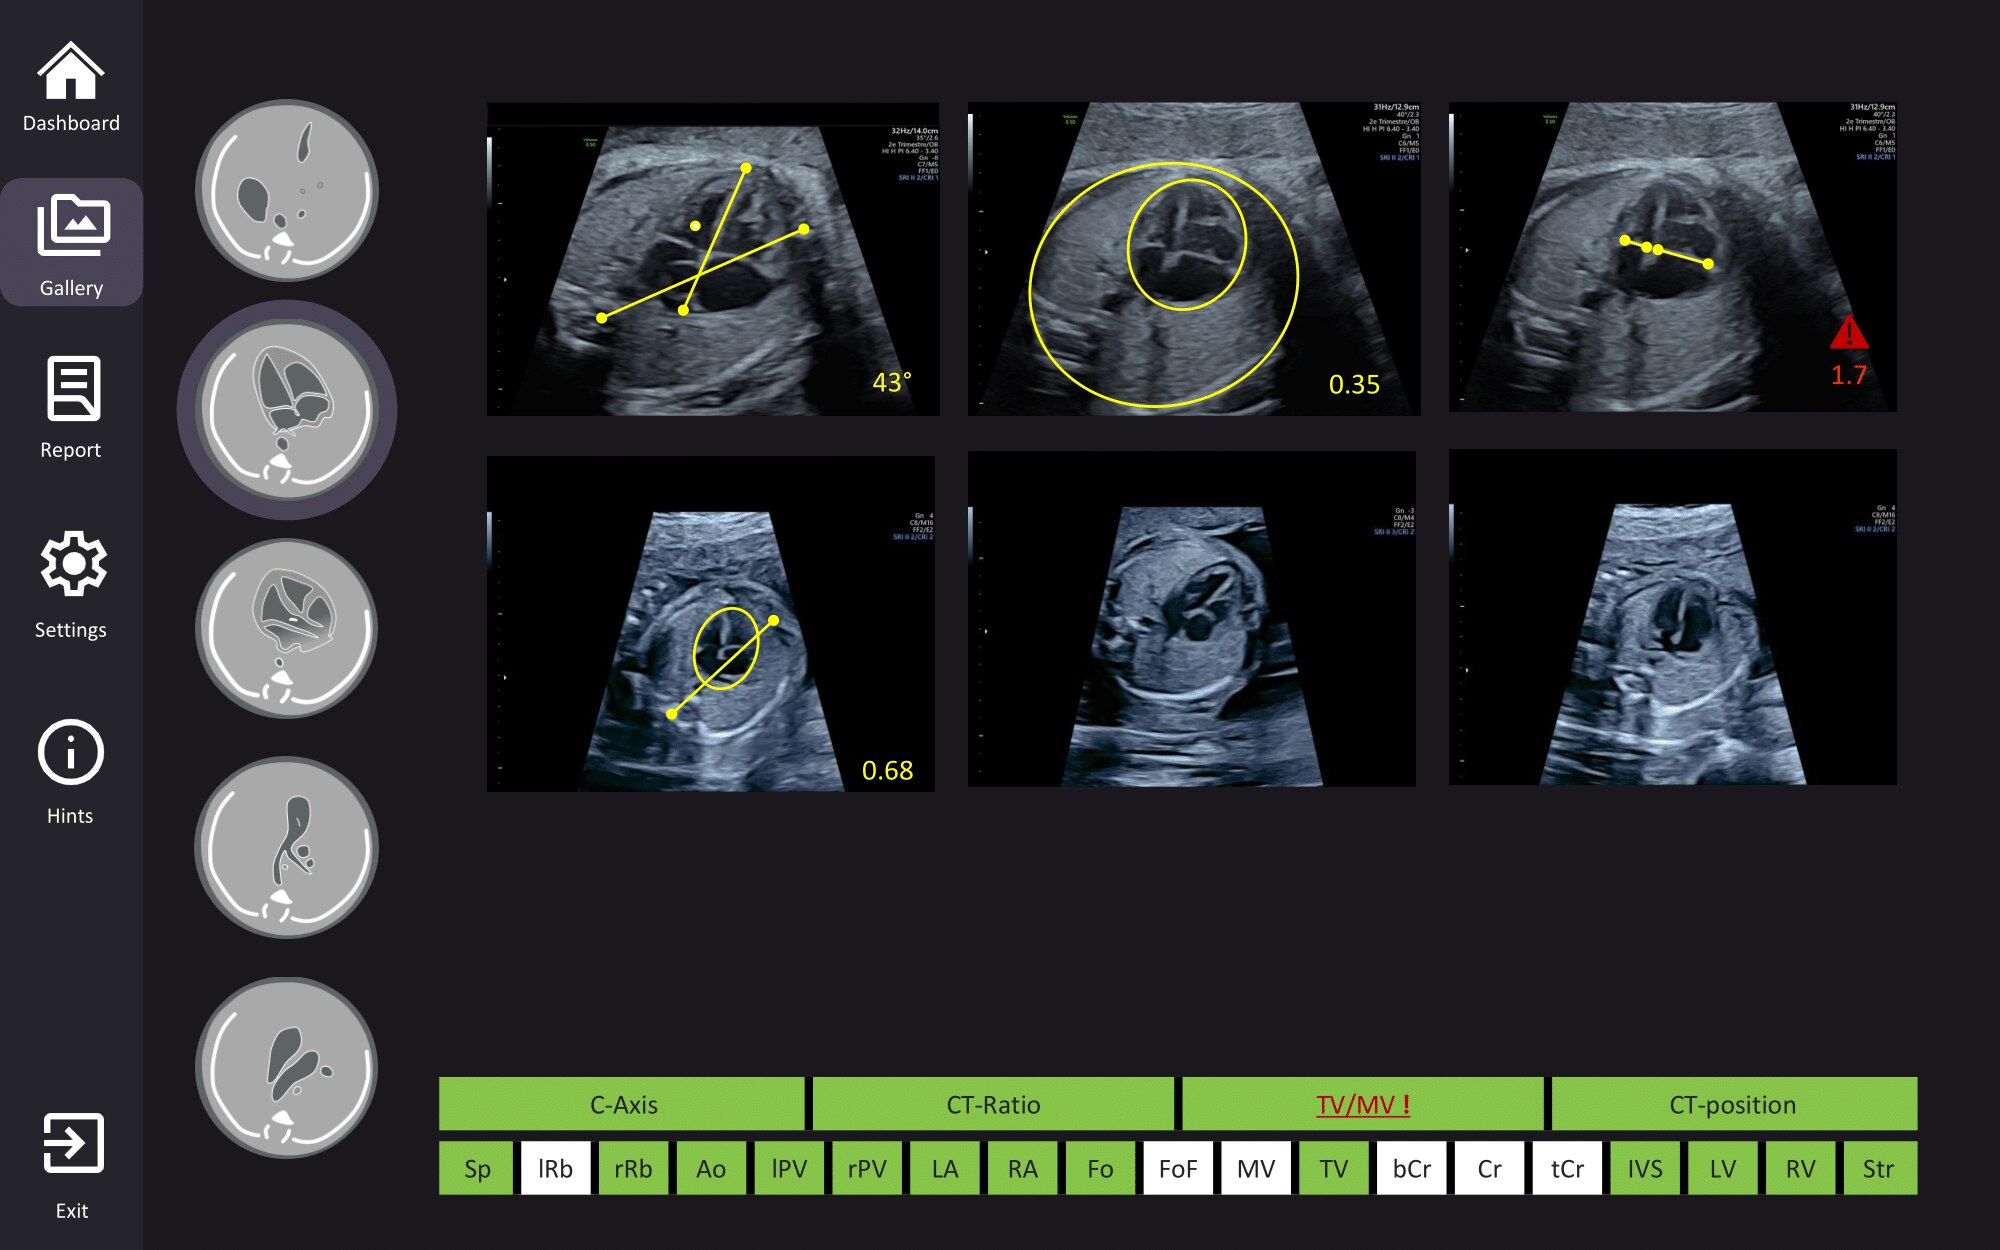

AI screening assistant for fetal heart and brain

Fetoly is the first real-time AI solution for fetal ultrasound, helping to ensure a complete and standardized examination. Integrating with most ultrasound systems, it provides instant feedback to help diagnostic confidence and help improve pregnancy outcomes.

• Instantly detects over 100 key fetal structures

• Automatic freeze and view selection

• Real-time ratios supporting the detection of pathologies